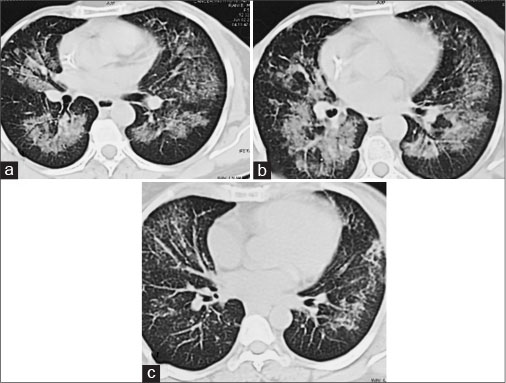

| Figure 3 Pretreatment computed tomography scan - axial high resolution sections in lung windows show diffuse perihilar groung glass haziness and peribronchial thickening in bilateral mid zones (a and b). Posttreatment high resolution sections show significant improvement in the interstitial pneumonitis with patchy residual ground glass haziness (c)